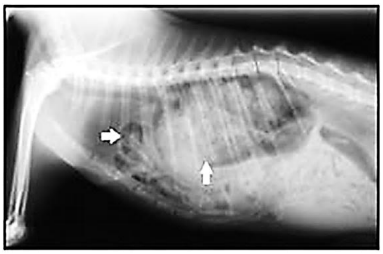

Foi atendido em um hospital veterinário um gato, sem raça definida, com 3,6 kg e dois anos de idade, não castrado, com histórico de atropelamento, dificuldade respiratória e emagrecimento progressivo há, aproximadamente, 15 dias. Após exame clínico, constataram-se dispneia, abafamento dos batimentos cardíacos e sons de borborigmos na região torácica. Para auxiliar no diagnostico, foi realizada uma radiografia simples, cuja imagem está apresentada na figura abaixo.

Exame radiográfico em projeção lateral

Com base nas informações do caso e na imagem radiográfica, o provável diagnóstico é de